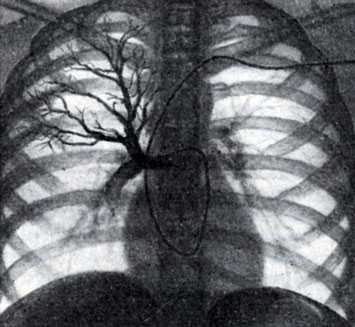

Для оценки функции легкого, его отдельных долей и сегментов предложена методика концевой, или терминальной ангиопульмонографии (Semisch, 1959; М. З. Упитер, 1962; Э. С. Шафер, 1964, и др.). Она заключается в медленном, плавном введении через зонд, заклиненный в субсегментарной артерии, 5—10 мл контрастного раствора. На 2—3-й секунде от начала введения при ощущении сопротивления производится одиночный снимок, на котором регистрируются артериальная венозная и капиллярная фазы легочного кровотока.

Концевая ангиопульмонография позволяет определить состояние периферического сосудистого русла. По степени изменения мелких сосудов и капилляров можно судить о характере и глубине нарушения функции легочной ткани (М. 3. Упитер, 1962).